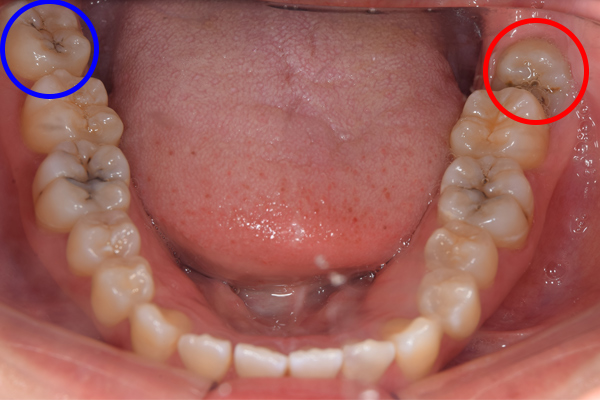

上顎はしっかり親知らずがはえています。下顎は右(青)はしっかりはえていますが、虫歯になっています。下顎の左(赤)は斜めにはえています。またこちらも虫歯になっています。

親知らずは、のどに近いですし、頬っぺたもありますので、なかなか磨くのが難しいですね。そのため、虫歯になりやすい傾向にあります。また、プラーク(歯垢)除去がしずらいため、親知らずの周りの歯茎が腫れたり、出血しやすくなります。